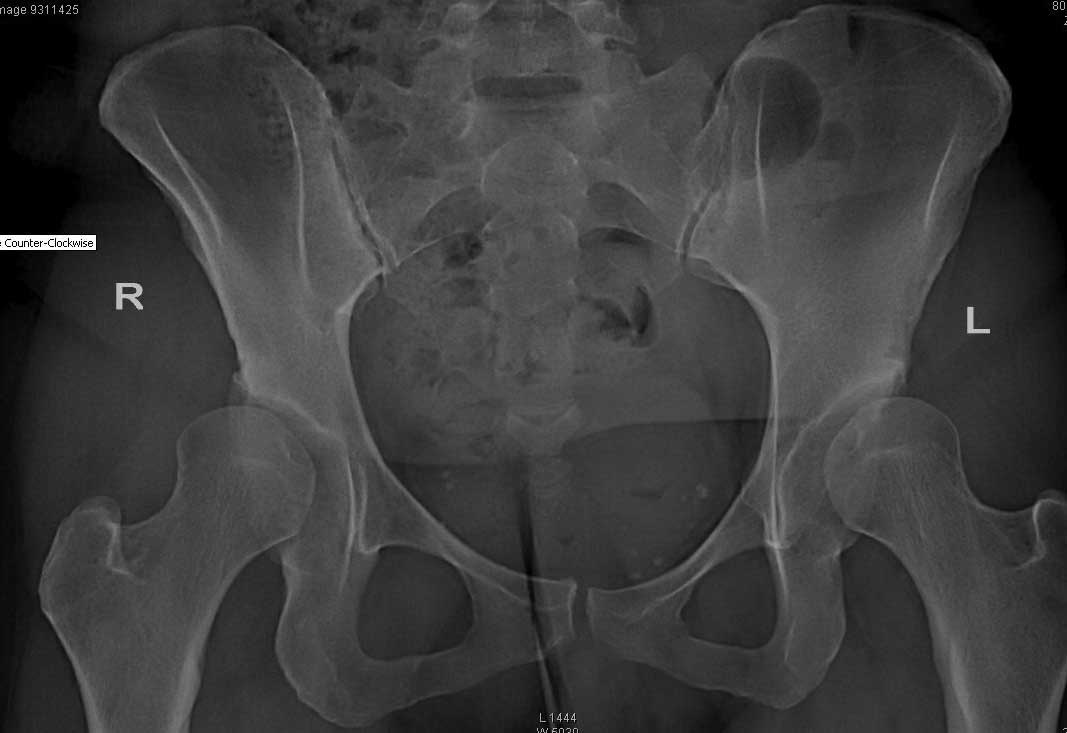

Пациентке 31 год. Р-гр прилагаю. Житель ЕС. консультировалась в Германии,Франции и Италии.

могут выполнить протезирование но советуют поискать специалистов занимающихся

остеотомиями таза.